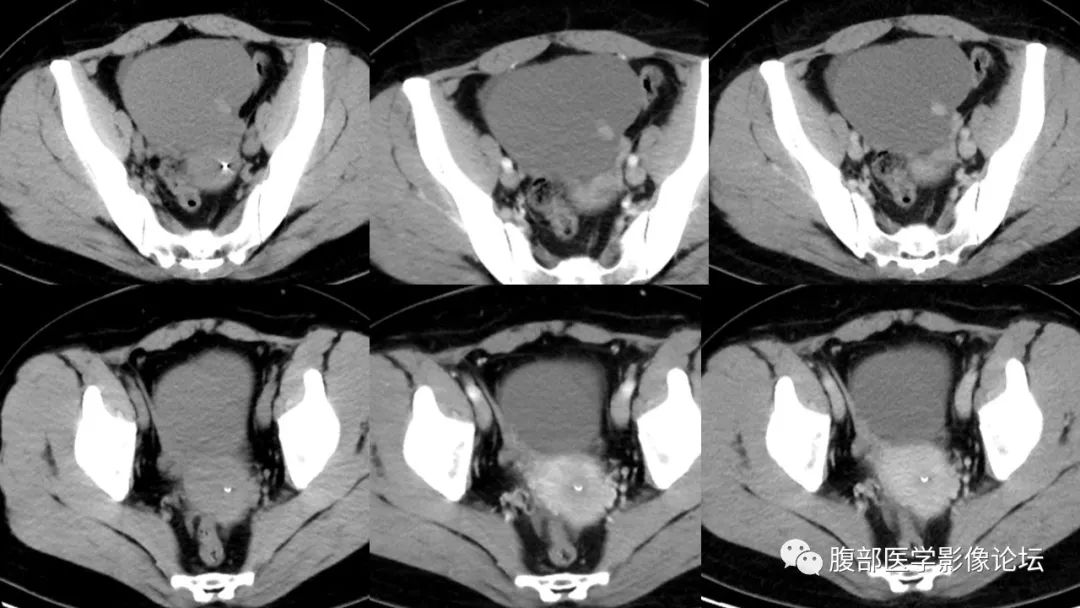

影像表现囊性或囊实性,可有分隔。囊壁可钙化,高密度囊肿是so特征性表现。增强扫描实性成分及分隔明显强化。核磁,so内粘性胶冻样或者出血信号复杂,t2低信号是so特征性表现。 医学百科网 | YxBaike.Com

冬天里的一把火:中年妇女,左侧附件区囊实性改变,多个囊腔目测密度不一,大小不一,实性病变内见钙化阴影,强化似明显。考虑卵巢甲状腺肿。鉴别囊腺瘤,成熟性畸胎瘤。 医学百科网 | YxBaike.Com

张文坦:中年女性,实验室肿标正常。右侧附件区囊性肿块,可见结节状稍高密度影,增强似乎没有强化,盆腔内少量积液,考虑SO。没有CT值诊断有点困难[偷笑][偷笑][偷笑],如果都是实性成分,轻微强化,考虑纤维—卵泡膜类细胞瘤。如果没有强化,结节状状高密度有强化,需要鉴别成熟性囊性畸胎瘤、透明细胞癌。

王鑫:右附件区囊实性病灶,平扫密度稍低,增强后实性成分轻中度强化,少量积液,考虑卵泡膜纤维瘤,卵泡膜细胞瘤,鉴别囊腺瘤,so